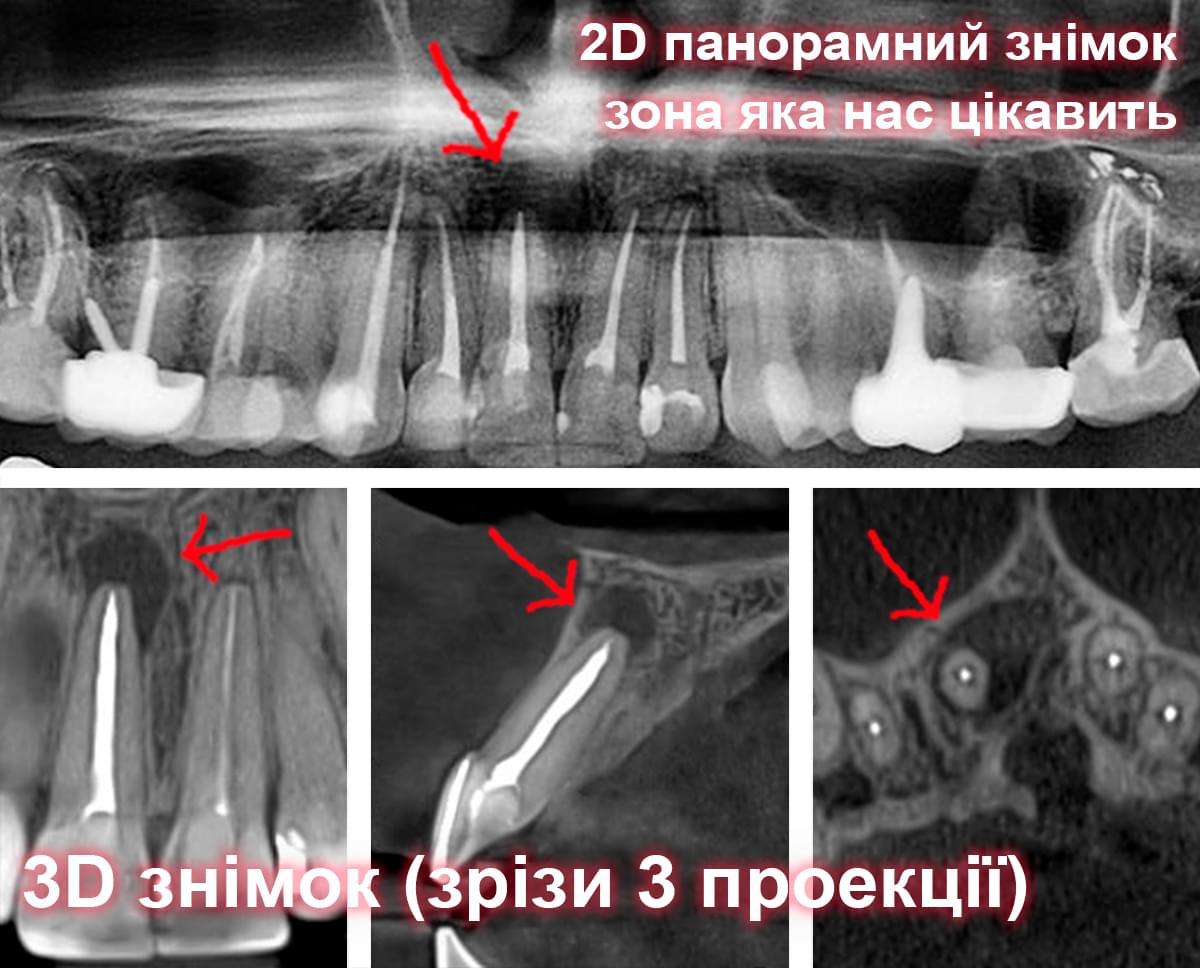

Головний недолік 2D-рентгену — це площинне зображення. Зуби, корені, щільна кістка та гайморові пазухи накладаються один на одного, створюючи «візуальний шум».

Візуальне порівняння (Кейс одного пацієнта)

Зуб — це не просто монолітний об'єкт, а складна система мікроканалів. На плоскому 2D-знімку вони часто перекривають один одного, створюючи ілюзію простої анатомії.

Непомічений канал — це джерело майбутньої інфекції та причина «загадкового» болю після лікування. Завдяки високій роздільній здатності обладнання MyRay, лікар бачить кожен мікронний канал ще до того, як візьме до рук інструмент.

Коли коріння «ховає сюрпризи» - Корені зубів часто мають складну кривизну, гачкоподібні закручення або розгалуження, які на звичайному 2D-знімку накладаються один на одного, створюючи ілюзію прямого каналу. На плоскій картинці неможливо побачити реальний об'єм та напрямок вигину, що критично важливо при видаленні «зубів мудрості» або ендодонтичному лікуванні. КТ MyRay дає змогу лікарю заздалегідь побачити 3D-геометрію кожного кореня, оцінити його близькість до нижньощелепного нерва чи гайморової пазухи та підібрати правильну тактику роботи. Це мінімізує ризики поломки інструменту в каналі або травмування сусідніх структур, перетворюючи складну хірургію на прогнозовану процедуру.